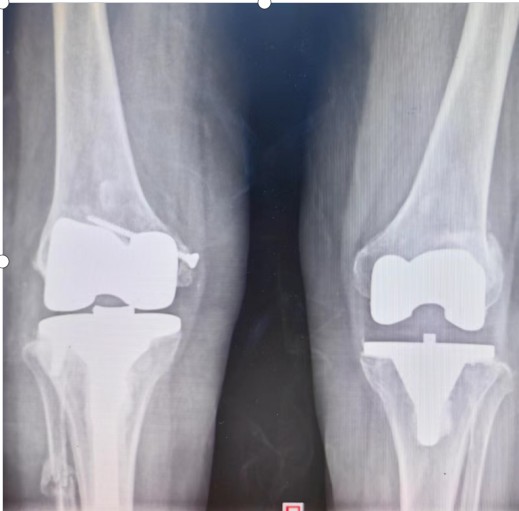

術(shù)前

術(shù)后

術(shù)后一年